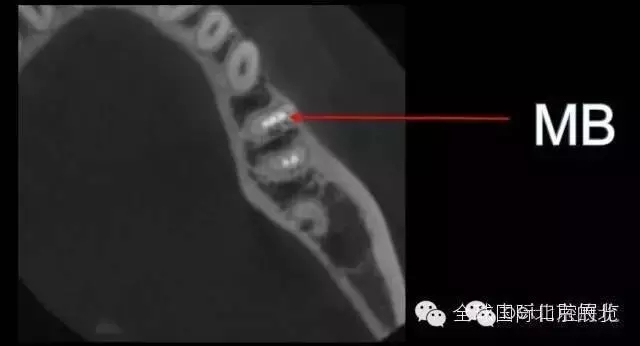

DB,DL.根管充填完成,樹脂封閉根管口,繼續(xù)探索未知的近中隱藏根管,所以決定拍1/4 CBCT確認(rèn)MB存在,

證實(shí)確實(shí)是遺漏了MB,

是遺漏了,但是又有新的問題出現(xiàn),無法找到根管口,我一般會(huì)用8#Kfile去尋找根管,CBCT上看就在眼前,但是我就是看不到,也無法進(jìn)入,此時(shí)操作也快一個(gè)小時(shí)了,患者也覺得累了,所以MB暫且停止尋找,因?yàn)橐泊_實(shí)無法進(jìn)入,所以把ML,MM根充完成,準(zhǔn)確測(cè)量長(zhǎng)度,AH-Plus,根管糊劑,涂布根管壁,冷牙膠依次充填完成暫封,下周繼續(xù)尋找失落的根管,同時(shí)也要把頰側(cè)楔缺的位置封閉好,防止再感染,再?zèng)]有橡皮障的保護(hù)下盡量減少感染機(jī)率。

去除暫封物繼續(xù)尋找MB,繼續(xù)尋找之前,用樹脂將根充完成的DB,DL根管口封閉,MB的位置暫時(shí)先不封,防止堵塞MB,剛開始還是找不到MB,然后從頰側(cè)的楔狀缺損入手才得以發(fā)現(xiàn)MB的入口,把楔缺擴(kuò)大去腐干凈。

終于找到MB了,然后把根管口MM,ML封閉,S3機(jī)擴(kuò),F(xiàn)1.04錐度牙膠試尖,期盼了好久的柳暗花明終于出現(xiàn)。